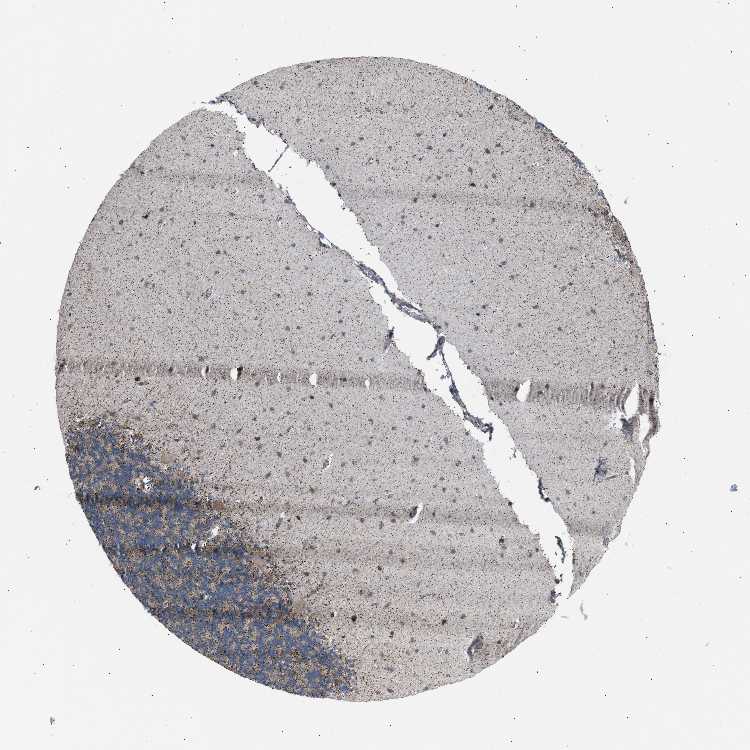

BRAIN CEREBELLUM Show tissue menu

CEREBELLUM - Expression summary

CEREBELLUM - Antibody stainingi

Antibody staining in the annotated cell types in the current human tissue is reported as not detected, low, medium, or high, based on conventional immunohistochemistry profiling in selected tissues. This score is based on the combination of the staining intensity and fraction of stained cells.

Each image is clickable and will lead to virtual microscopy that enables deeper exploration of all samples and also displays staining intensity scores, fraction scores and subcellular localization as well as patient and tissue information for each sample.

Antibody CAB019309

Purkinje cells High

Cells in granular layer Low

Cells in molecular layer Medium